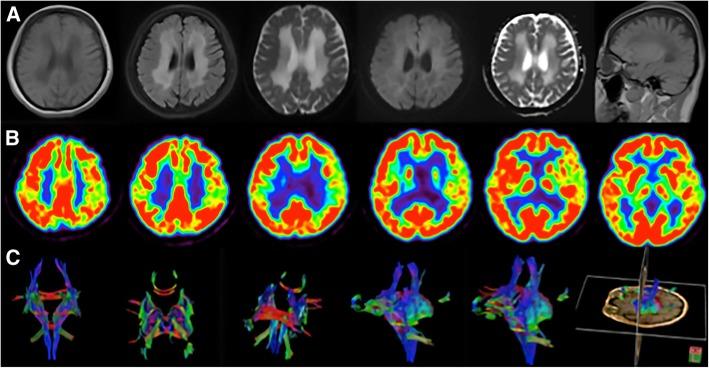

Vanishing white matter disease (VWMD) is one of the most prevalent inherited leukoencephalopathies, which generally presents in childhood as a progressive disorder while less beginning in adulthood. The present report describes the clinical, neuroimaging, and genetic findings of a female patient with adult-onset VWMD. In addition, to provide a clearer delineation of the clinical and genetic characteristics of female adult-onset VWMD patients, 32 genetically confirmed female adult-onset EIF2B-mutated cases are summarized.

The patient described here suffered from long-term menometrorrhagia prior to manifesting progressive neurological impairments that included tremors, bilateral pyramidal tract injury, cerebellar ataxia, and dementia. To the best of our knowledge, this is the first female patient with adult-onset VWMD suffering from long-term menometrorrhagia attributed to the c.254 T > A and c.496A > G mutations in the EIF2B2 gene; the c.496A > G mutation has not been reported in previous studies. The patient also exhibited metabolic dysfunction. The present findings widen the spectrum of phenotypic heterogeneity observed in VWMD patients.

The present report summarizes 33 female patients with adult-onset VWMD to provide an overview of the clinical and genetic characteristics of this disorder and ovarioleukodystrophy. The mean age of clinical onset in female patients with adult-onset VWMD was 36.8 years and the neurological symptoms primarily included motor and cognitive dysfunction such as paraparesis, cerebellar ataxia, and executive deficits. In addition, ovarian failure occurred in all of these female patients and usually preceded the neurological symptoms. Furthermore, several patients also suffered from metabolic dysfunction. All 33 patients had mutations on EIF2B1-5, and of these, the c.338 G > A mutation in the EIF2B5 gene (p.Arg113His) was the most common. These findings suggest that clinicians should be aware of adult-onset forms of VWMD as well as its typical magnetic resonance imaging (MRI) and clinical characteristics although this pathology is usually recognized as a pediatric disorder. No curative treatment is presently available, and thus early recognition is important to prevent triggering events and to allow for genetic counseling.

脑白质消融症(VWMD)是最常见的遗传性脑白质病之一,通常在儿童期表现为进行性疾病,而在成年期发病较少。本报告描述了一位成年起病 VWMD 女性患者的临床、神经影像学和遗传学发现。此外,为了更清楚地阐明女性成年起病 VWMD 患者的临床和遗传特征,总结了 32 例经基因证实的女性成年起病 EIF2B 突变病例。

本文描述的患者在出现进行性神经功能障碍之前,长期存在月经过多,包括震颤、双侧锥体束损伤、小脑共济失调和痴呆。据我们所知,这是首例成年起病 VWMD 女性患者,因 EIF2B2 基因 c.254T> A 和 c.496A> G 突变而长期月经过多;以前的研究中未报道过 c.496A> G 突变。患者还表现出代谢功能障碍。本研究结果拓宽了 VWMD 患者表型异质性的范围。

本报告总结了 33 例女性成年起病 VWMD 患者,以概述该疾病和卵巢脑白质营养不良的临床和遗传特征。女性成年起病 VWMD 患者的平均发病年龄为 36.8 岁,神经症状主要包括运动和认知功能障碍,如截瘫、小脑共济失调和执行功能缺陷。此外,所有这些女性患者均出现卵巢功能衰竭,且通常早于神经症状。此外,一些患者还患有代谢功能障碍。所有 33 例患者均有 EIF2B1-5 基因突变,其中 EIF2B5 基因 c.338G> A 突变(p.Arg113His)最为常见。这些发现表明,尽管这种病理通常被认为是儿科疾病,但临床医生应该意识到 VWMD 的成年起病形式及其典型的磁共振成像(MRI)和临床特征。目前尚无治愈方法,因此早期识别很重要,可以预防触发事件并进行遗传咨询。